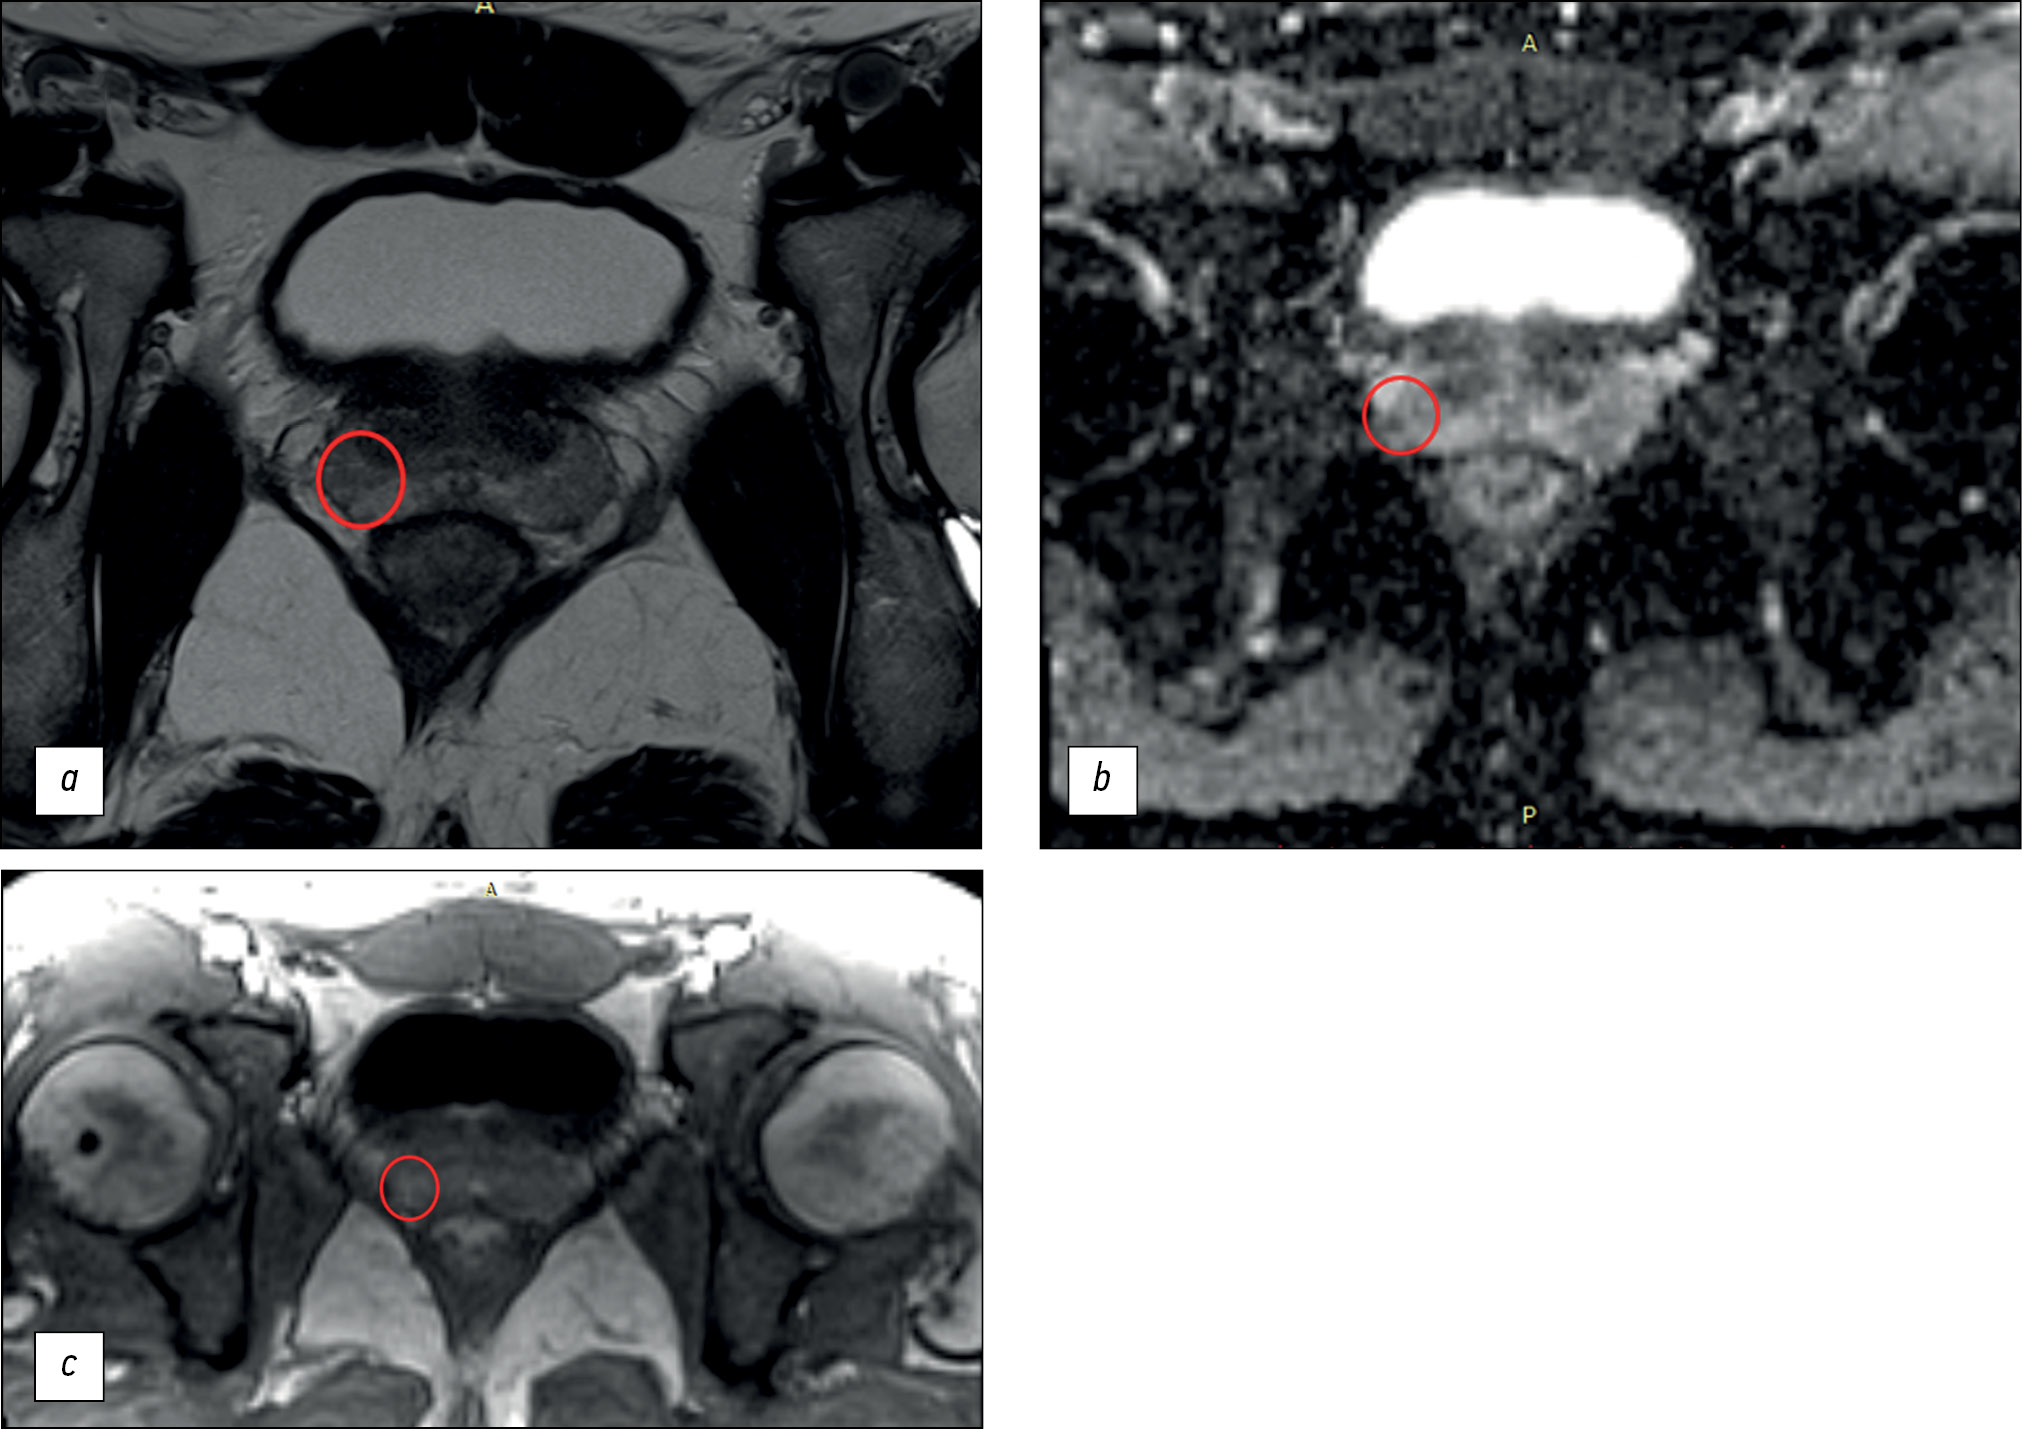

The main finding of our study is that the diagnostic power of prostate MRI is low. The maximum diagnostic accuracy for lesion detection was 70.1%, with a sensitivity of ≤62.5% and specificity of ≤74.6%. Based on the obtained values, MRI cannot be considered a reliable method for early diagnosis because of its suboptimal sensitivity (Fig. 1).

Fig. 1. An example of a false-positive result of biparametric magnetic resonance imaging: a ― T2-weighted image in the axial plane: in the lateral posterior segment of the peripheral zone of the left lobe in the middle part of the prostate gland there is a focus of reduced signal corresponding to the zone of diffusion restriction; b is a map of the measured diffusion coefficient. This lesion was characterized by the physician as PI-RADS5. According to multifocal biopsy, prostate tissue without signs of tumor growth.